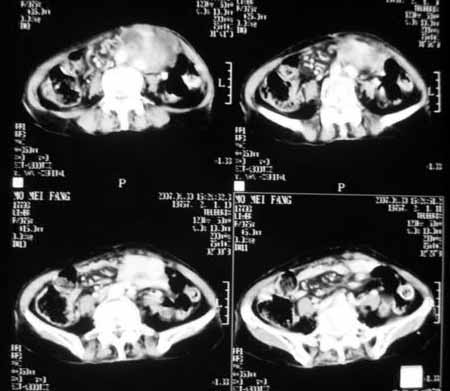

以下是引用天南地北在2007-4-30 17:42:00的发言:[br]增强扫描显示腹主动脉给包绕、推移。肿块不规则强化,[br]修正我在平扫的诊断[br]支持考虑:间叶源性肿瘤可能性大

以下是引用zyx168在2007-4-30 23:24:00的发言:[br]考虑:间叶源性肿瘤可能性大